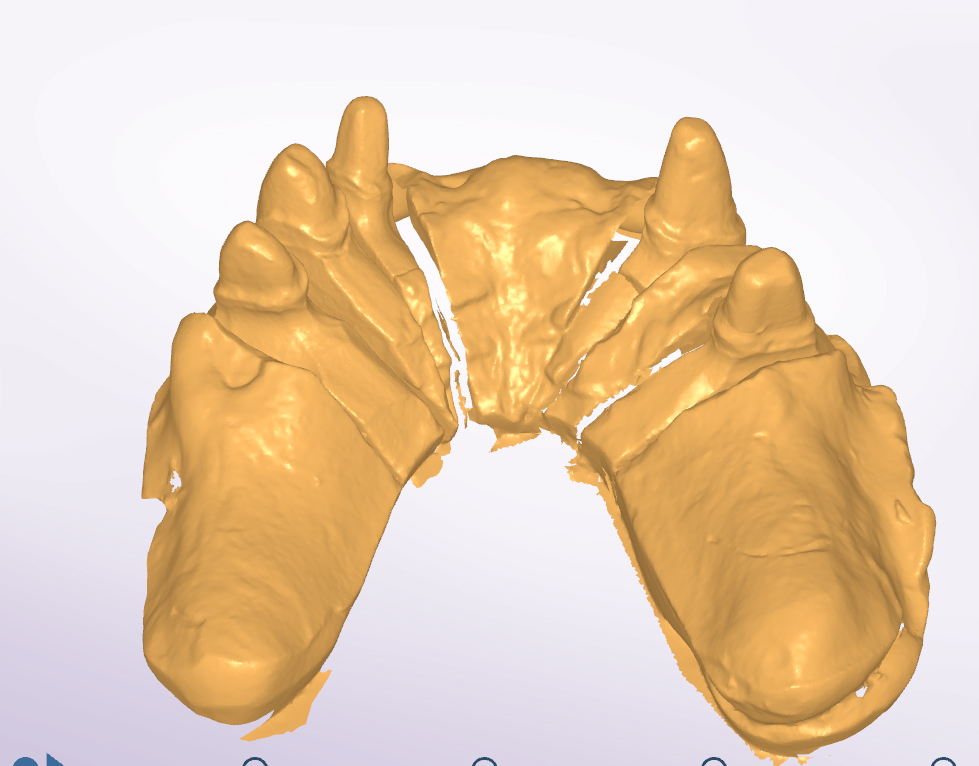

Teleskopierende Brücken im digitalen Ablauf hergestellt.